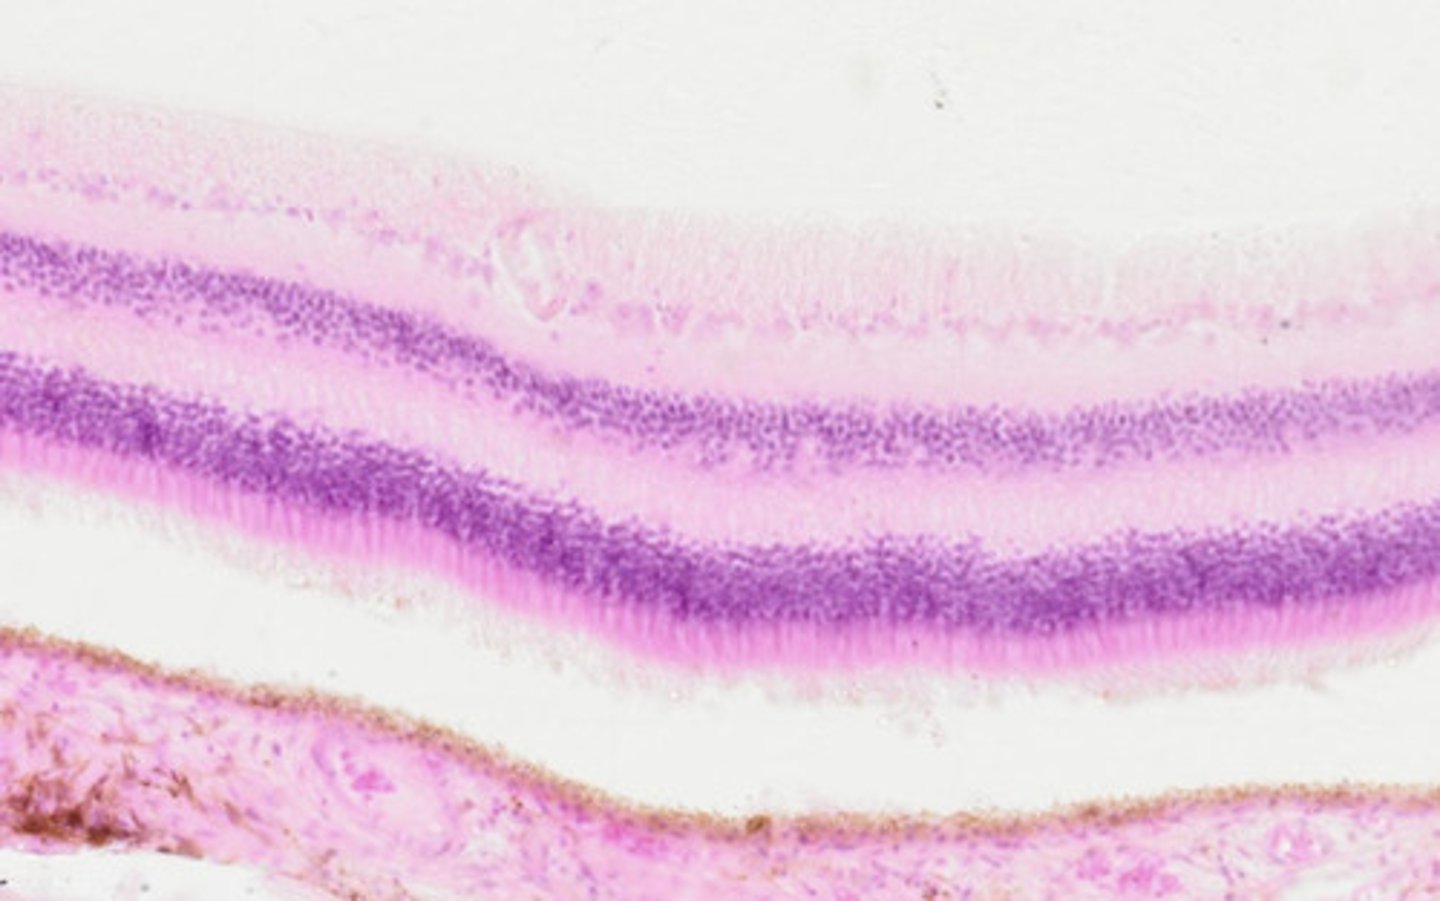

Oko - siatkówka (H+E)